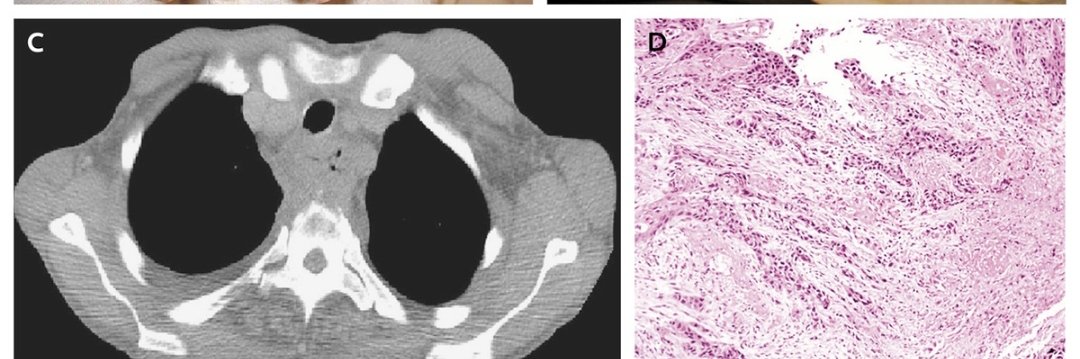

What is the diagnosis?

Cardiac tamponade

Tension hydrothorax

Diaphragmatic eventeration

Pulmonary hydatid disease

Lymphangiomyomatosis Image

Answer

Cardiac tamponade resolved after removal of 6 liters of pus from the right chest Image

A 43-year-old man

👉 respiratory distress after a 3-week illness

👉 h/o alcoholism but no other serious illness

👉 RR 34, HR 120 ,BP 80/50

👉oxygen saturation of 86% while breathing ambient air.

Read 13 tweets